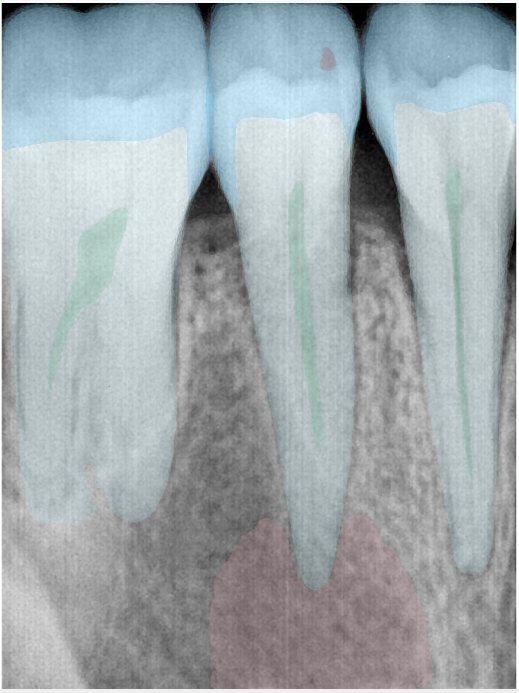

第二版算法问题测试

| 第一版 | 第二版 | 是否解决 | |

|---|---|---|---|

![]() | ![]() ![]() 边角识别有问题 龋齿识别不全 牙髓识别不全 | ![]() | 解决 |

![]() | ![]() 边角识别有问题 识别信息有误 自查(牙冠识别不全) | ![]() | 解决 |

![]() | ![]() ![]() 边角识别有误 大范围填充识别遗漏 | ![]() | 解决 |

![]() | ![]() 识别信息不全 | ![]() | 解决 |

![]() | ![]() ![]() 边角问题 牙胶识别不全 牙冠识别不全 | ![]() | 解决 |

![]() 换图片 | ![]() | ![]() 牙冠部分稍微白了一些就识别成小范围修补,部分判断异常 | 部分解决,修复类略敏感,牙冠部分稍微白了一些就识别成小范围修补,部分判断异常。 |

![]() | ![]() ![]() 牙冠识别不全 牙髓不全 根尖炎龋齿识别有误 | ![]() | 解决 |

![]() | ![]() | ![]() | 解决 |

![]() 换图片 | ![]() | ![]() | 解决 |

![]() | ![]() 牙冠识别有误 | ![]() | 解决 |

![]() 换图片 | ![]() ![]() 边角识别有误 | ![]() 修复类敏感 | 部分解决,图像过白,导致修复类判断异常。 |

![]() 换图片 | ![]() 牙冠识别不全 | ![]() 修复类敏感 | 部分解决,图像过白,导致修复类判断异常 |

结论:修复类出现了不鲁棒的情况,后续需要加入轮廓的扩充数据进行增强。